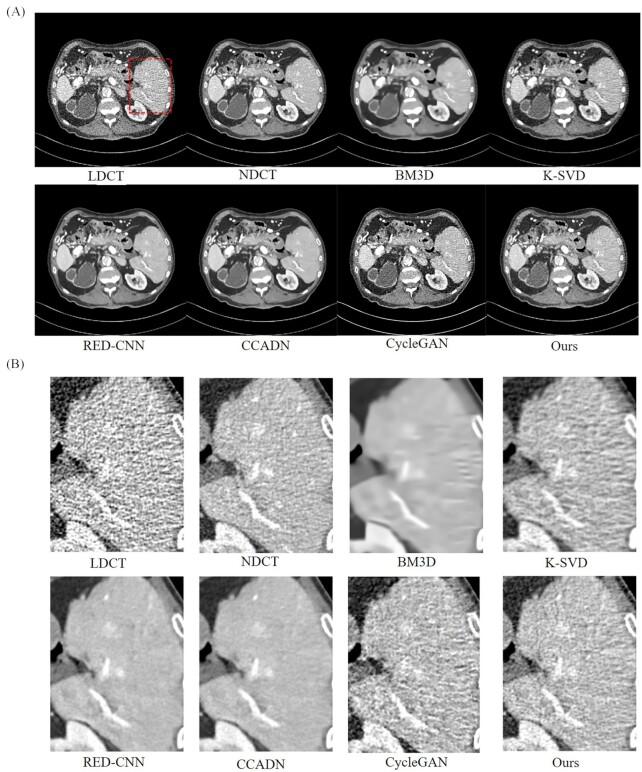

Low-dose computed tomography (LDCT) denoising is an indispensable procedure in the medical imaging field, which not only improves image quality, but can mitigate the potential hazard to patients caused by routine doses. Despite the improvement in performance of the cycle-consistent generative adversarial network (CycleGAN) due to the well-paired CT images shortage, there is still a need to further reduce image noise while retaining detailed features. Inspired by the residual encoder-decoder convolutional neural network (RED-CNN) and U-Net, we propose a novel unsupervised model using CycleGAN for LDCT imaging, which injects a two-sided network into selective kernel networks (SK-NET) to adaptively select features, and uses the patchGAN discriminator to generate CT images with more detail maintenance, aided by added perceptual loss. Based on patch-based training, the experimental results demonstrated that the proposed SKFCycleGAN outperforms competing methods in both a clinical dataset and the Mayo dataset. The main advantages of our method lie in noise suppression and edge preservation.

低剂量计算机断层扫描(LDCT)去噪是医学成像领域不可或缺的一项操作,它不仅能提高图像质量,还能减轻常规剂量对患者造成的潜在危害。尽管由于配对良好的CT图像短缺,循环一致生成对抗网络(CycleGAN)的性能有所提升,但仍需要在保留细节特征的同时进一步降低图像噪声。受残差编码器-解码器卷积神经网络(RED-CNN)和U-Net的启发,我们提出了一种用于LDCT成像的新型无监督模型,该模型使用CycleGAN,将双边网络注入选择性内核网络(SK-NET)以自适应选择特征,并使用PatchGAN鉴别器生成具有更多细节保留的CT图像,同时添加感知损失作为辅助。基于基于补丁的训练,实验结果表明,所提出的SKFCycleGAN在临床数据集和梅奥数据集中均优于竞争方法。我们方法的主要优点在于噪声抑制和边缘保留。